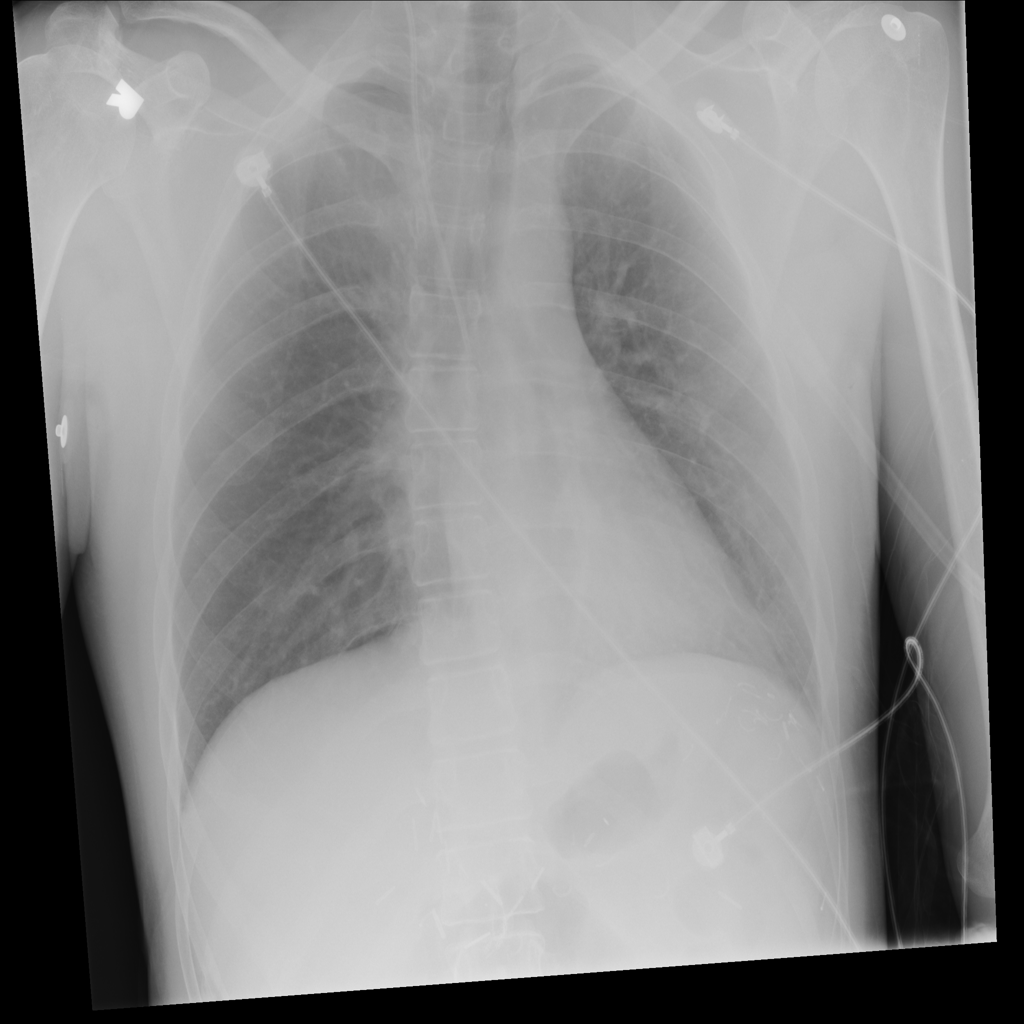

PAT-4639 · IMG-012Pneumothorax

PAT-4639 · IMG-012

AP